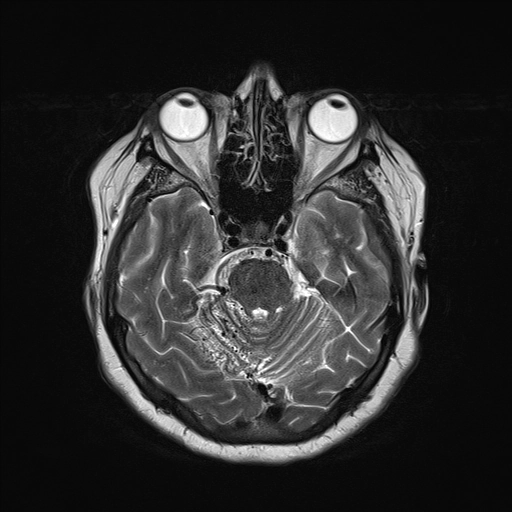

• Dị dạng thông Động-Tĩnh mạch não (Brain Arteriovenous Malformation - AVM)

• Dị dạng phình tĩnh mạch Galen (Vein of Galen aneurysmal malformations - VGAMs)